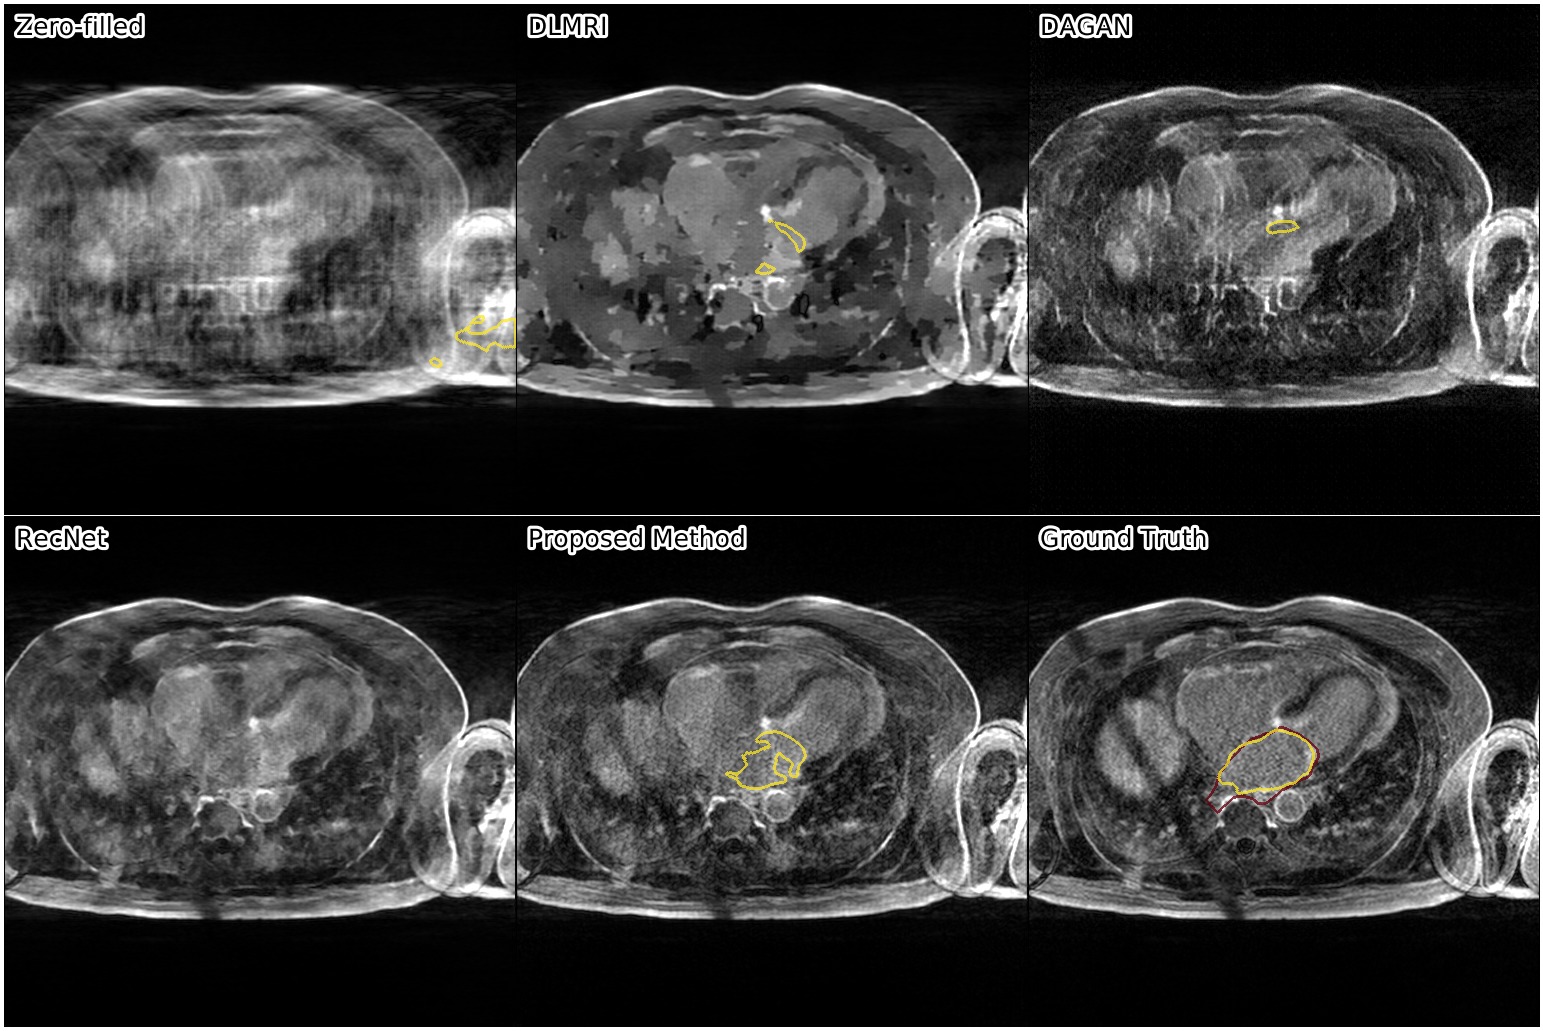

We show the results of our evaluation in Table 1, and a sample reconstruction in Figure 2. RecNet performed best in terms of PSNR, which is expected as its training objective directly corresponds to this metric, but its reconstructions were over-smoothed. DLMRI had the lowest MOS, with its reconstructions showing heavy oil paint artifacts. DAGAN, combining MSE loss with a visual loss function without any further precautions, suffered from low PSNR. While its reconstructions also looked sharp, they were noisy and often displayed aliasing artifacts, which was reflected in a lower MOS compared to our method. Our proposed approach achieved significantly444Significance determined by a two-sided paired Wilcoxon signed-rank test at . higher mean opinion score than all other methods, while still maintaining high PSNR. Reconstructions obtained by our method appeared sharper with better contrast. Moreover, our method achieved the highest SIS close to segmentation performance on the ground truth data, which indicated that the segmented objects were clearly visible in the reconstructed images.

The following images show more samples for 8-fold undersampling. For each of the seven patients of the test set, a random slice showing the left atrium was selected. The contour of the predicted segmentation of left atrium is shown in yellow, the contour of the ground truth segmentation in red.